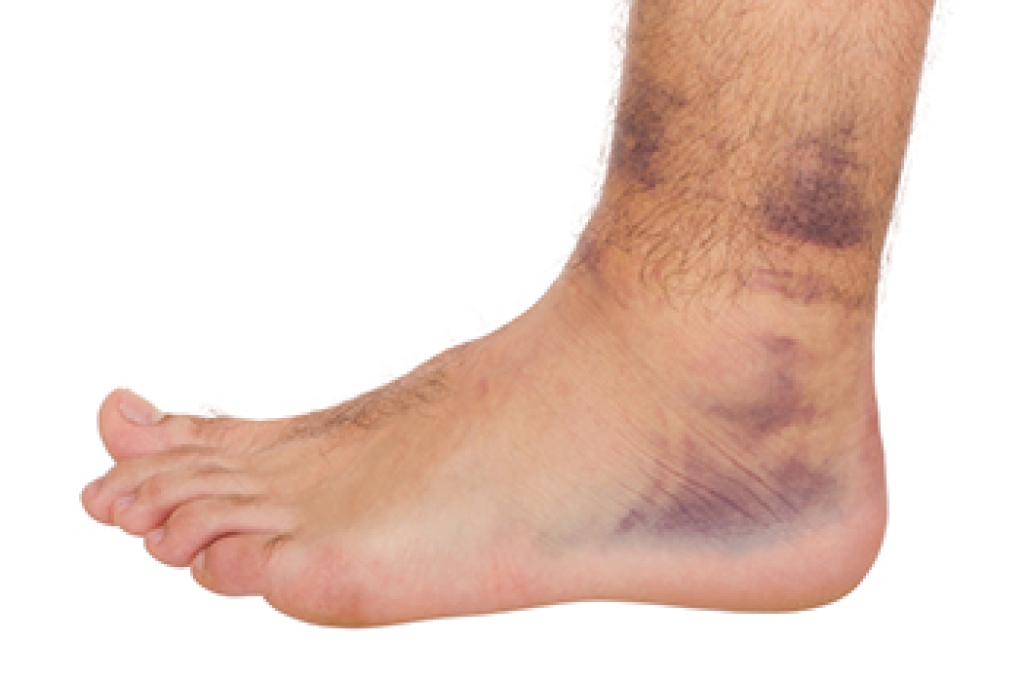

A blister on the foot can become infected when bacteria enter through broken skin, often caused by friction from tight shoes or repetitive motion. An infected blister may appear red, swollen, and filled with cloudy fluid. The surrounding area may feel warm or tender. Attempting to pop or drain a blister increases the risk of deeper infection and possible tissue damage. If untreated, the infection can spread to surrounding tissue or bone, leading to serious complications. A podiatrist can properly drain an infected blister in a sterile manner, prescribe necessary medication, and assess whether further care, such as wound cleaning, is needed. A podiatrist can also determine underlying causes, like poorly fitting shoes or biomechanical issues, that contribute to recurring blisters. If you believe you have an infected blister on your foot, it is suggested that you make an appointment with a podiatrist for a diagnosis and safe, sterile treatment.

A foot blister is a small fluid-filled pocket that forms on the upper-most layer of the skin. Blisters are filled with clear fluid and can lead to blood drainage or pus if the area becomes infected.

- Redness